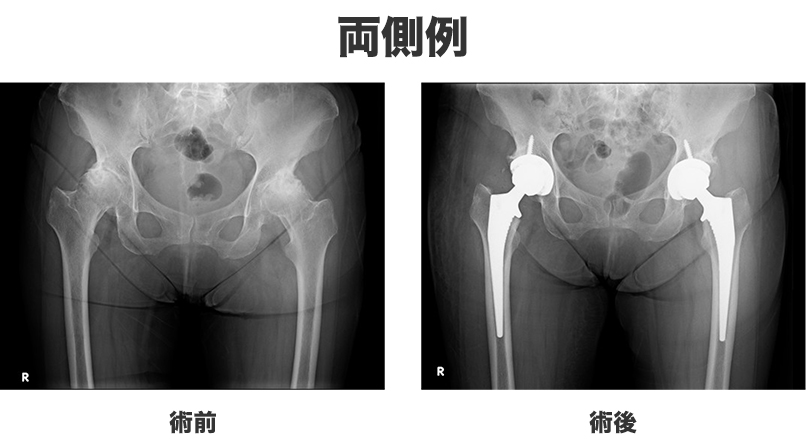

公益財団法人股関節研究振興財団新・股関節がよくわかる本Web版。